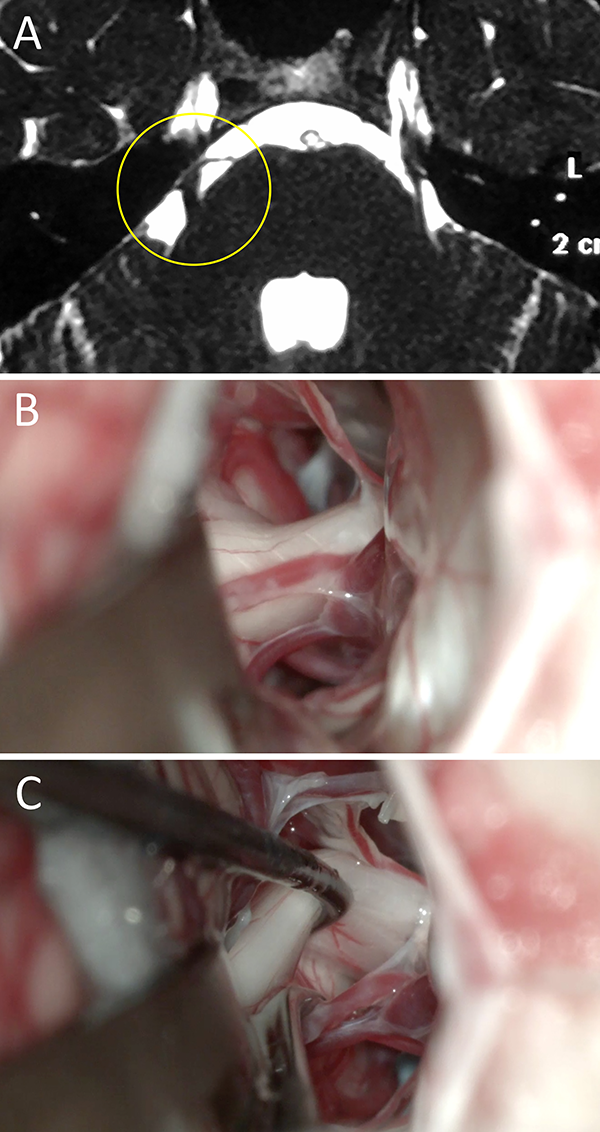

Figura 1:

Mujer de 34 años de edad consulta a neurólogo de cabecera por presentar cuadro compatible por relato con NT típica. Se realizó una RM donde se objetivo un claro CNV del lado derecho. Por esto, se interconsulta a nuestro equipo neuroquirúrgico. Se decidió DNV en virtud al cuadro clínico-radiológico. En el intraoperatorio se certificó el CNV. La paciente evolucionó favorablemente con remisión del cuadro doloroso. A) RM preoperatoria; B) hallazgo intraoperatorio; C) colocación de teflón. NT: neuralgia trigeminal; RM: resonancia magnética; CNV: conflicto neurovascular; DNV: descompresiva neurovascular.